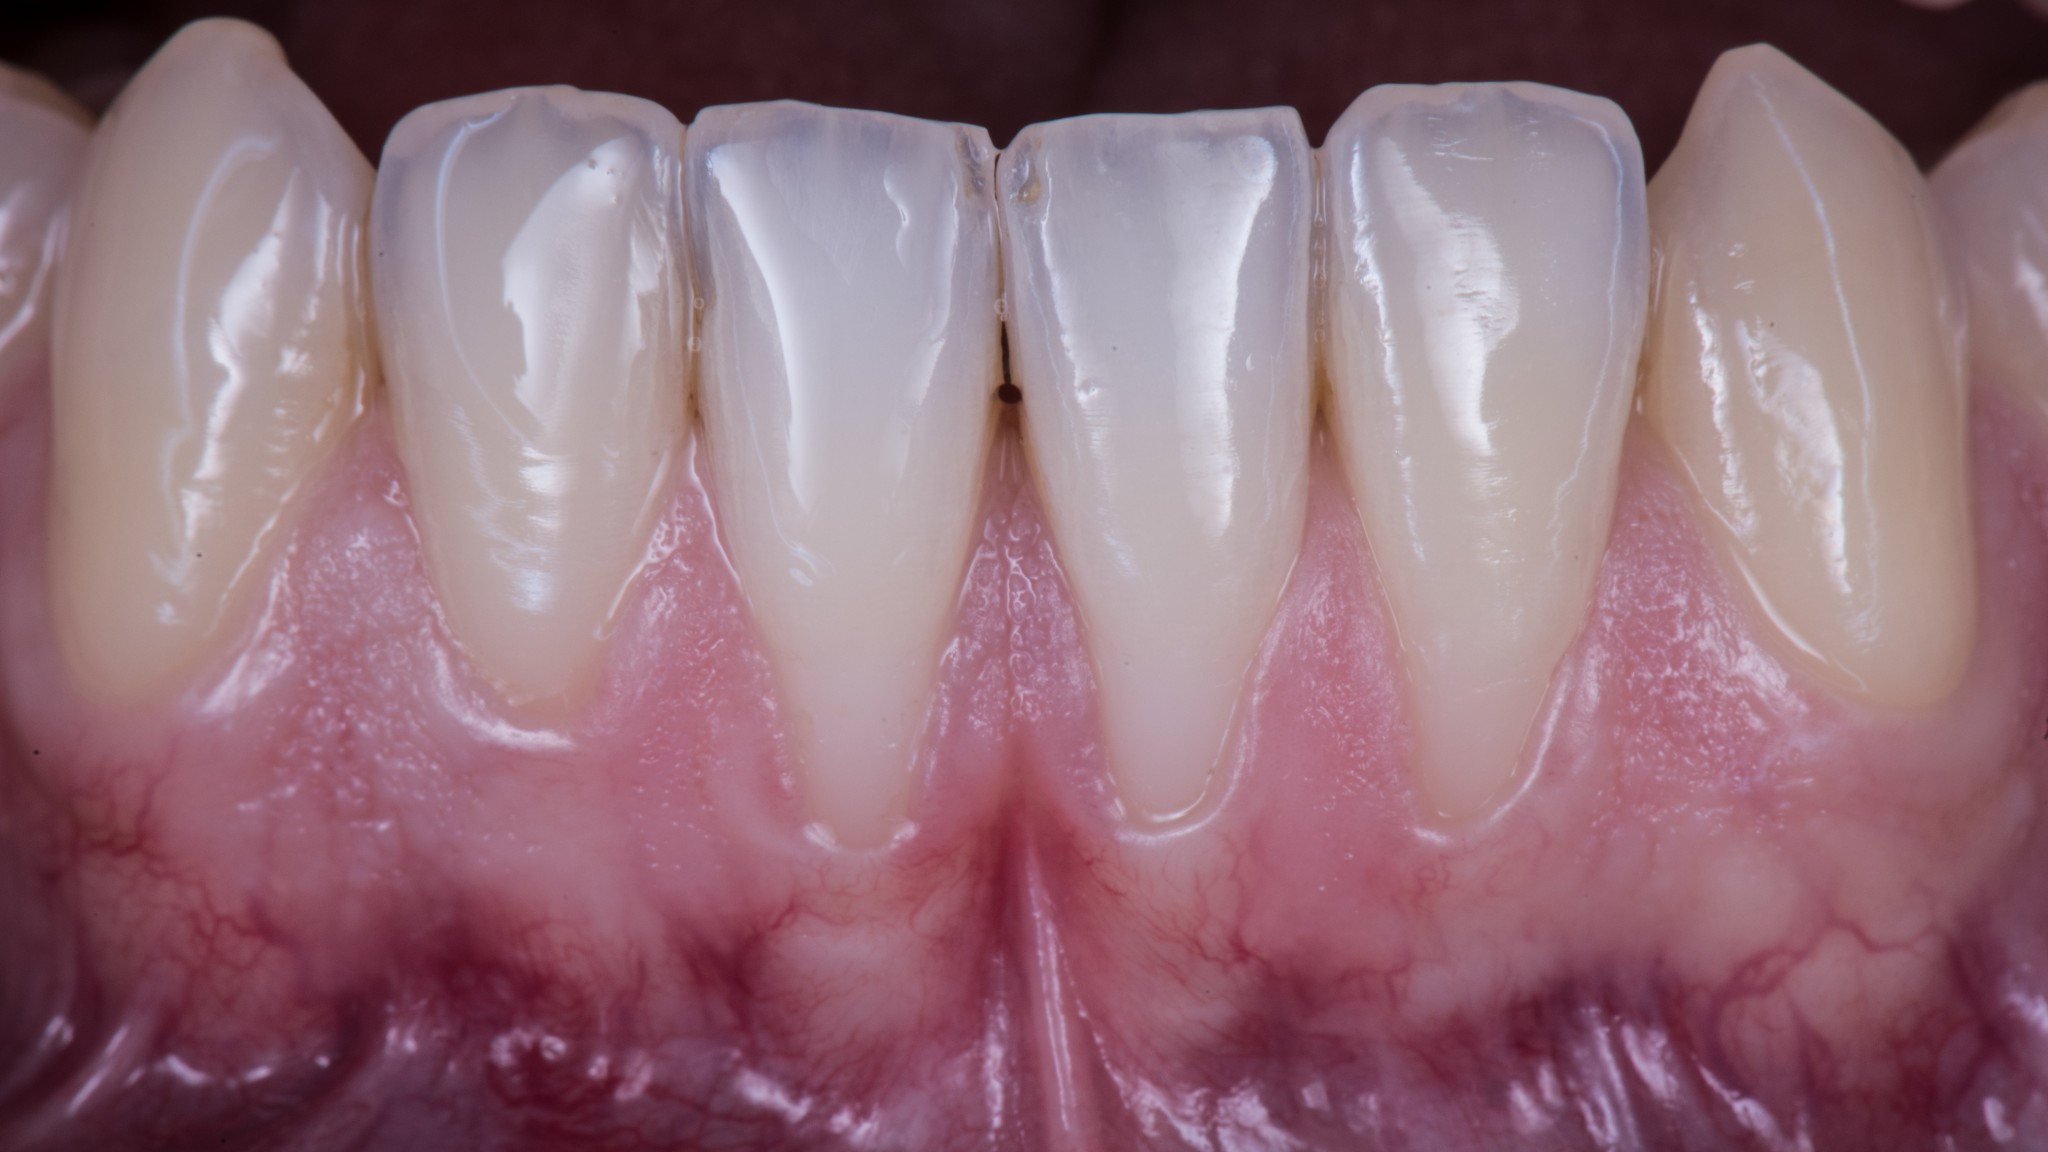

Guarda che bel caso:

Osserva attentamente dove sono le inserzioni muscolari e dove attacca il frenulo. Dicevamo che la zona più merdosa è proprio il quinto sestante perché la mucosa è sempre estremamente sottile ed è l’unico settore anatomico dove c’è un muscolo vero coi controcazzi. Il muscolo mentale.